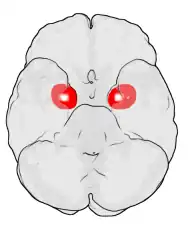

Миндалевидное тело (лат. corpus amygdaloideum), ами́гдала[1] — область мозга миндалевидной формы, находящаяся в белом веществе височной доли полушария под скорлупой, примерно на 1,5—2,0 см сзади от височного полюса. В мозге два миндалевидных тела — по одному в каждом полушарии[2]. Миндалевидное тело играет ключевую роль в формировании эмоций, в частности, страха. У пациента, миндалевидное тело которого оказалось полностью разрушено вследствие болезни Урбаха — Вите, наблюдалось отсутствие страха[3][4][5]. Миндалевидное тело также играет важную роль в функционировании памяти, принятии решений и эмоциональных реакциях[6]. Миндалевидное тело является частью лимбической системы, относится к подкорковым обонятельным центрам.

Кроме разницы в размерах, существуют другие различия между полами. Была изучена активация миндалевидного тела при просмотре фильмов ужасов у мужчин и женщин. Результаты исследования показали, что у разных полов активируются различные полушария. Повышенная активность наблюдалась у мужчин в правом полушарии, в то время как у женщин — в левом[20]. Также исследования показали, что женщины в среднем запоминают эмоционально насыщенные события лучше, чем мужчины[21].